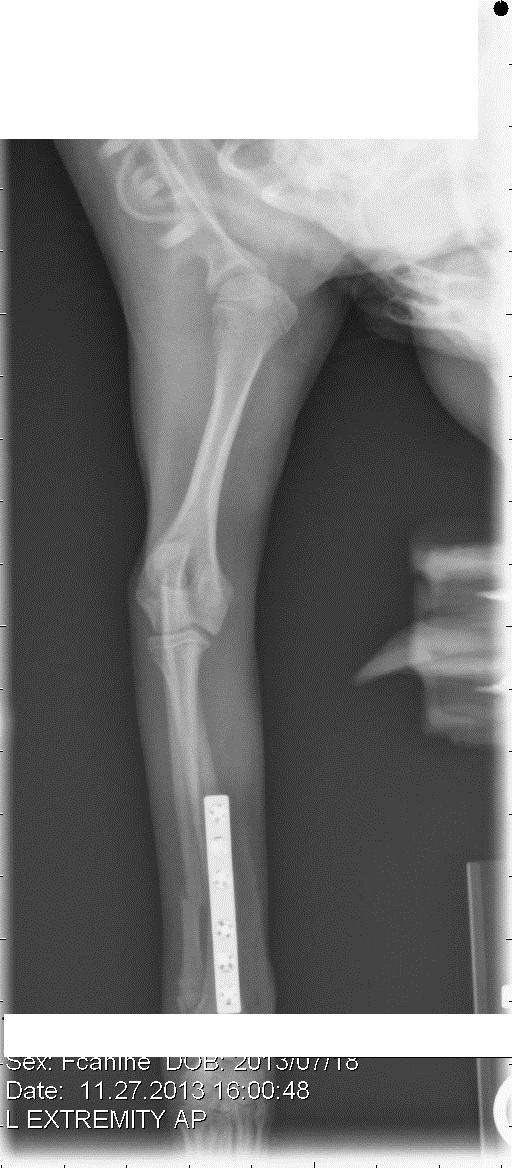

Ну да, у нас тоже счастливо скакала. И вот на чем: (первый снимок сделан перед операцией, после снятия гипса)

Сходили снова к вету, сняли повязку. Лапа выглядит нормально, собака на нее понемногу наступает. Про зону роста вет сказал, что она начинается на несколько миллиметров после последнего болта. Пластину все-таки будут снимать через какое-то время. В общем-то, принципиально это тот же аппарат Илизарова с поперечными винтами, только внутри. Локтевую кость не скрепили, сказали, что без надобности.

Что меня слегка напрягает: если щенку четыре месяца - ему ещё расти и расти; спица росту костей не помешала бы, а вот пластина - как-то я себе это плохо представляю. Зависит от того как она наложена и какого она размера. У вас перелом расположен близко к зоне роста. Попросите правда снимок, и проконсультируйтесь по этому вопросу.

По-моему нормально сделали. Локтевая срастётся; про пластину согласна - лучше убрать через пару месяцев.